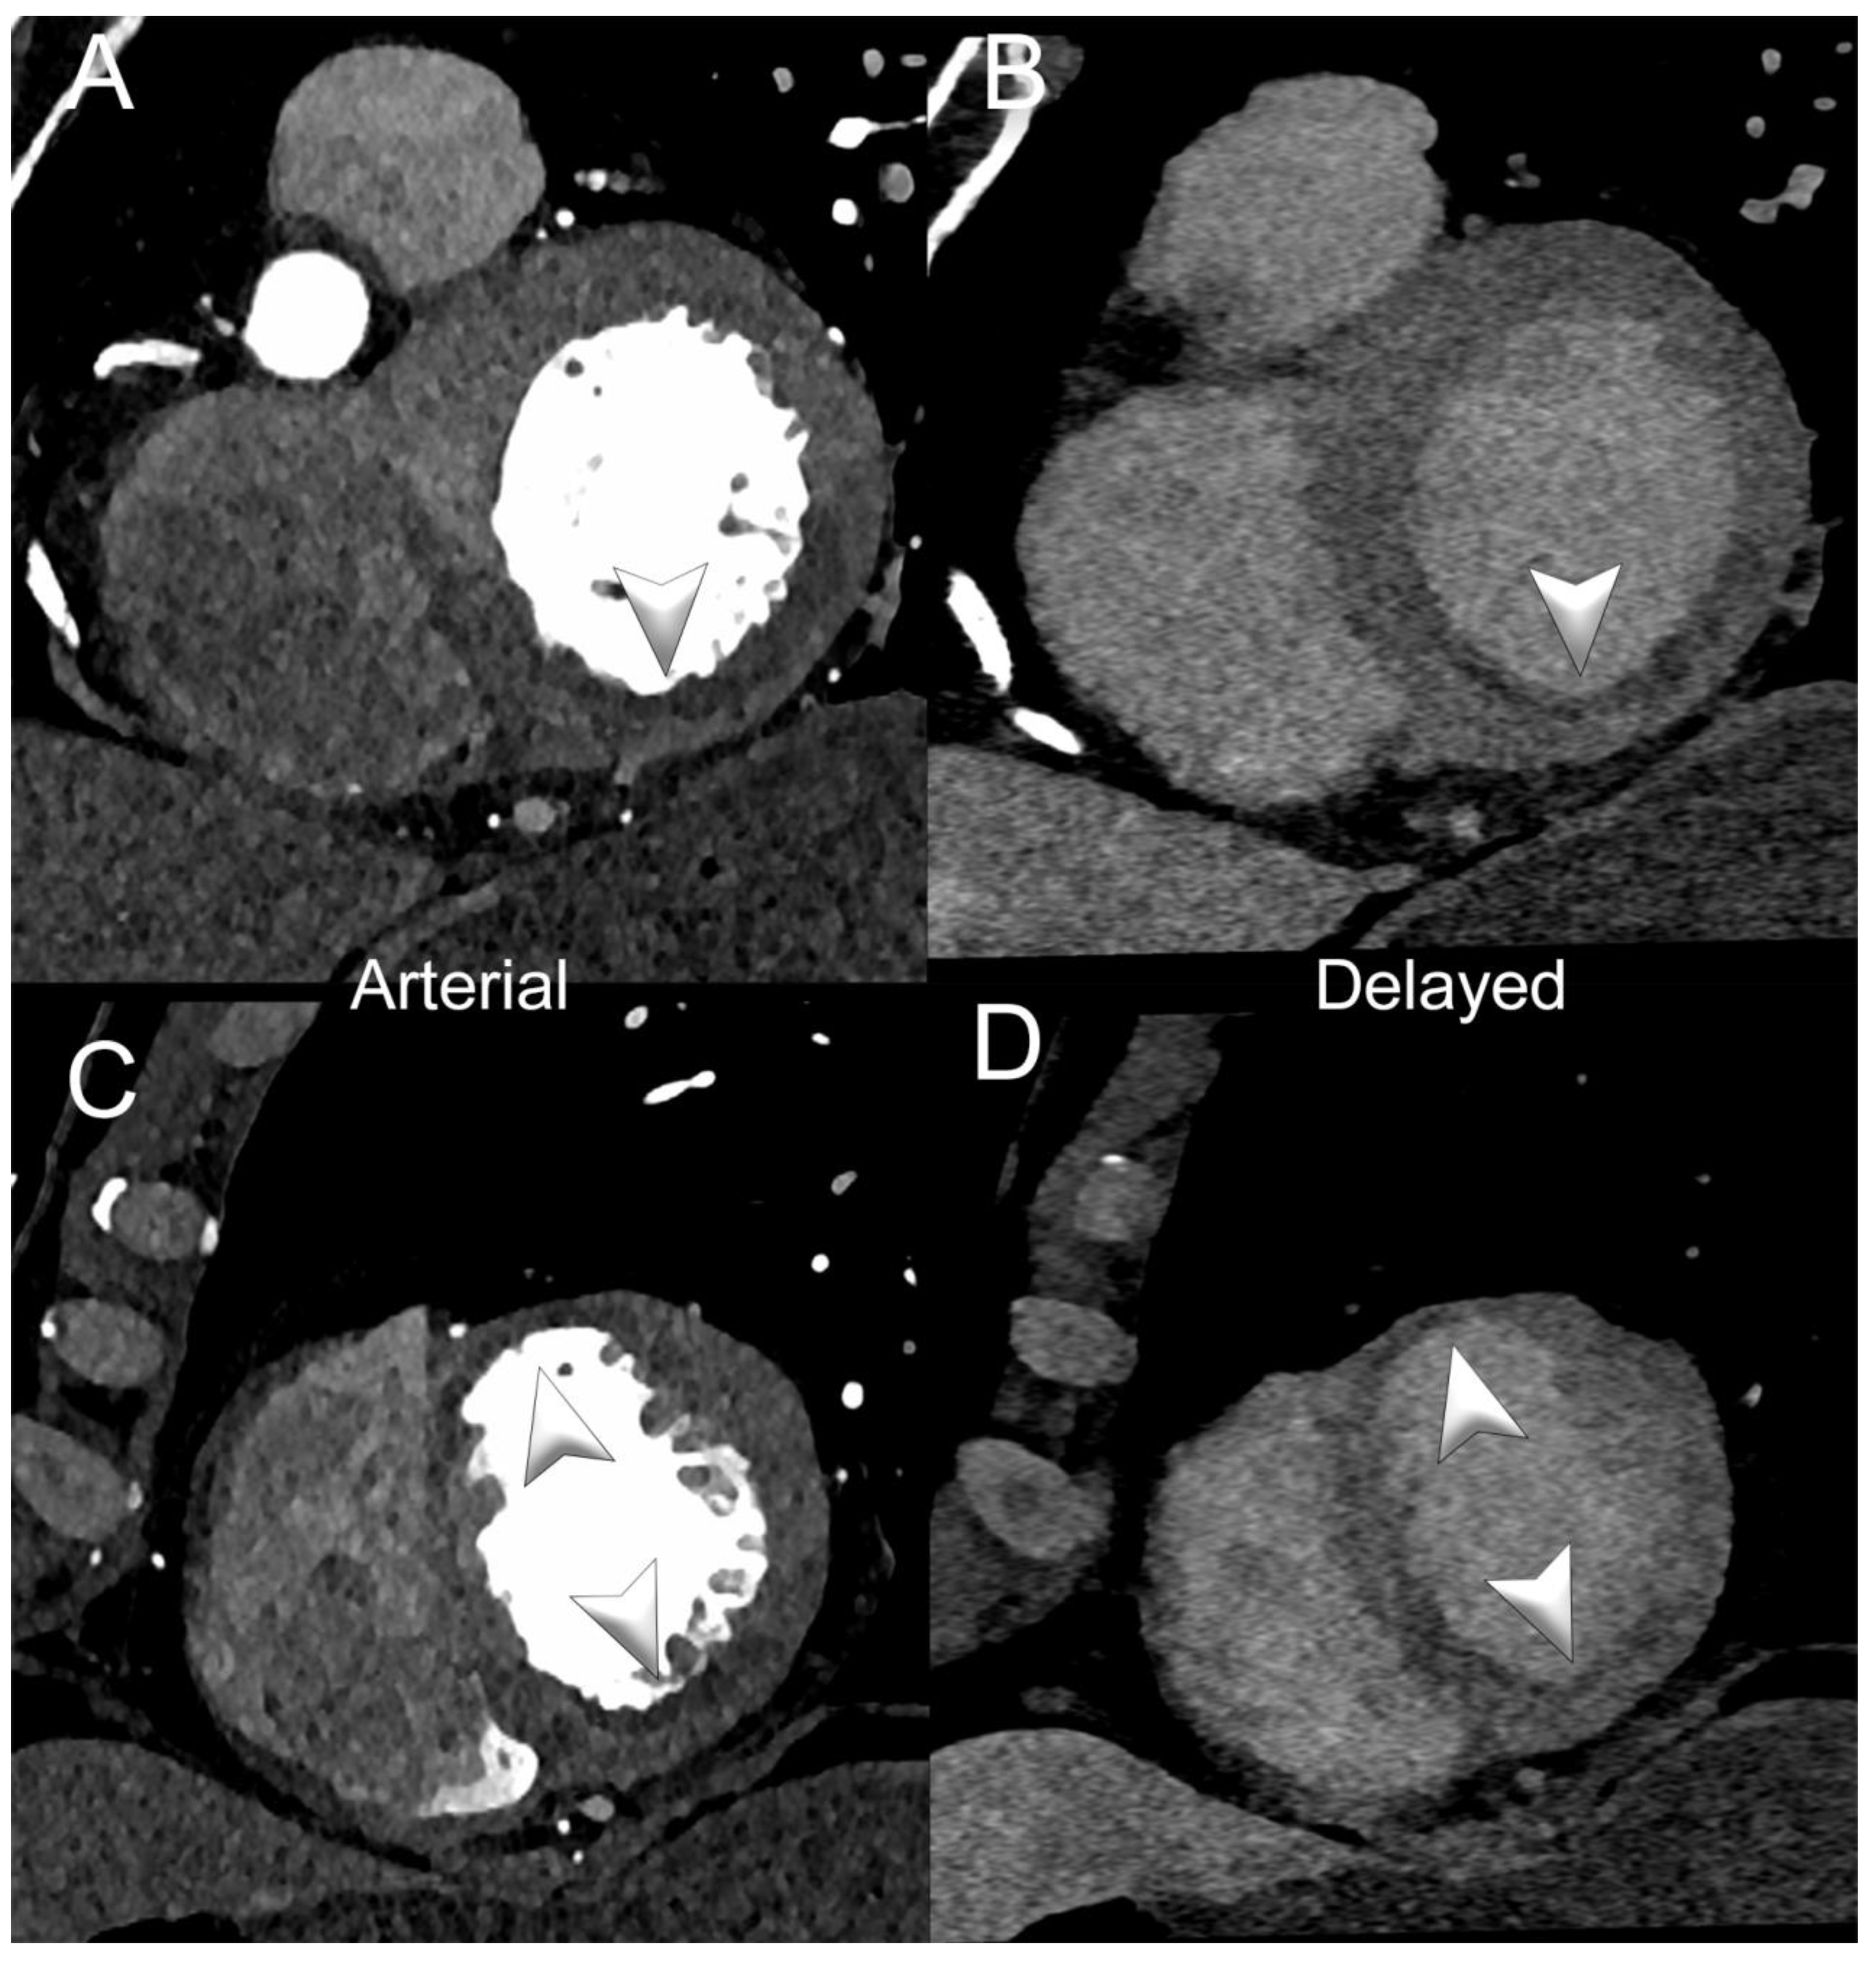

- Polacin, M.; Templin, C.; Manka, R.; Alkadhi, H. Photon-counting computed tomography for the diagnosis of myocardial infarction with non-obstructive coronary artery disease. Eur. Heart J.-Case Rep. 2022, 6, ytac028. [Google Scholar] [CrossRef] [PubMed]